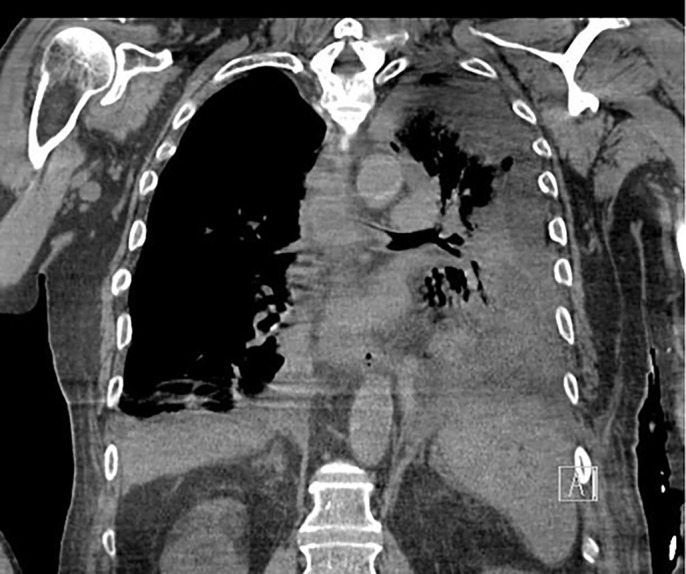

Case description: This report presents a 76-year-old man who presented to the emergency department after a history of several syncopal episodes and was found to be in complete heart block. Two days later, he acutely developed abdominal distention and coffee ground emesis. As the medical team was able to gather more history from the patient and his family, it was revealed that he had associated vomiting with his episodes of syncope. CT scan of the abdomen and pelvis demonstrated pneumomediastinum concerning for esophageal perforation. His clinical status subsequently deteriorated. He was intubated and a temporary transvenous pacer was placed before being transferred to our facility for emergent surgery.